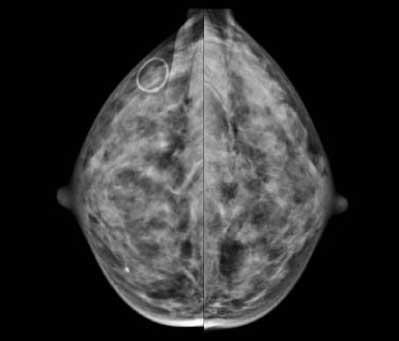

Recent studies have found that dense breast tissue is a strong independent risk factor for breast cancer. Breasts are composed of fat and fibroglandular tissue. Dense breast fibroglandular tissue appears white on a mammogram. Abnormalities and tumors also appear white on mammograms, causing them to be difficult to spot in dense breasts until the cancers are much larger and possibly in advanced stages.